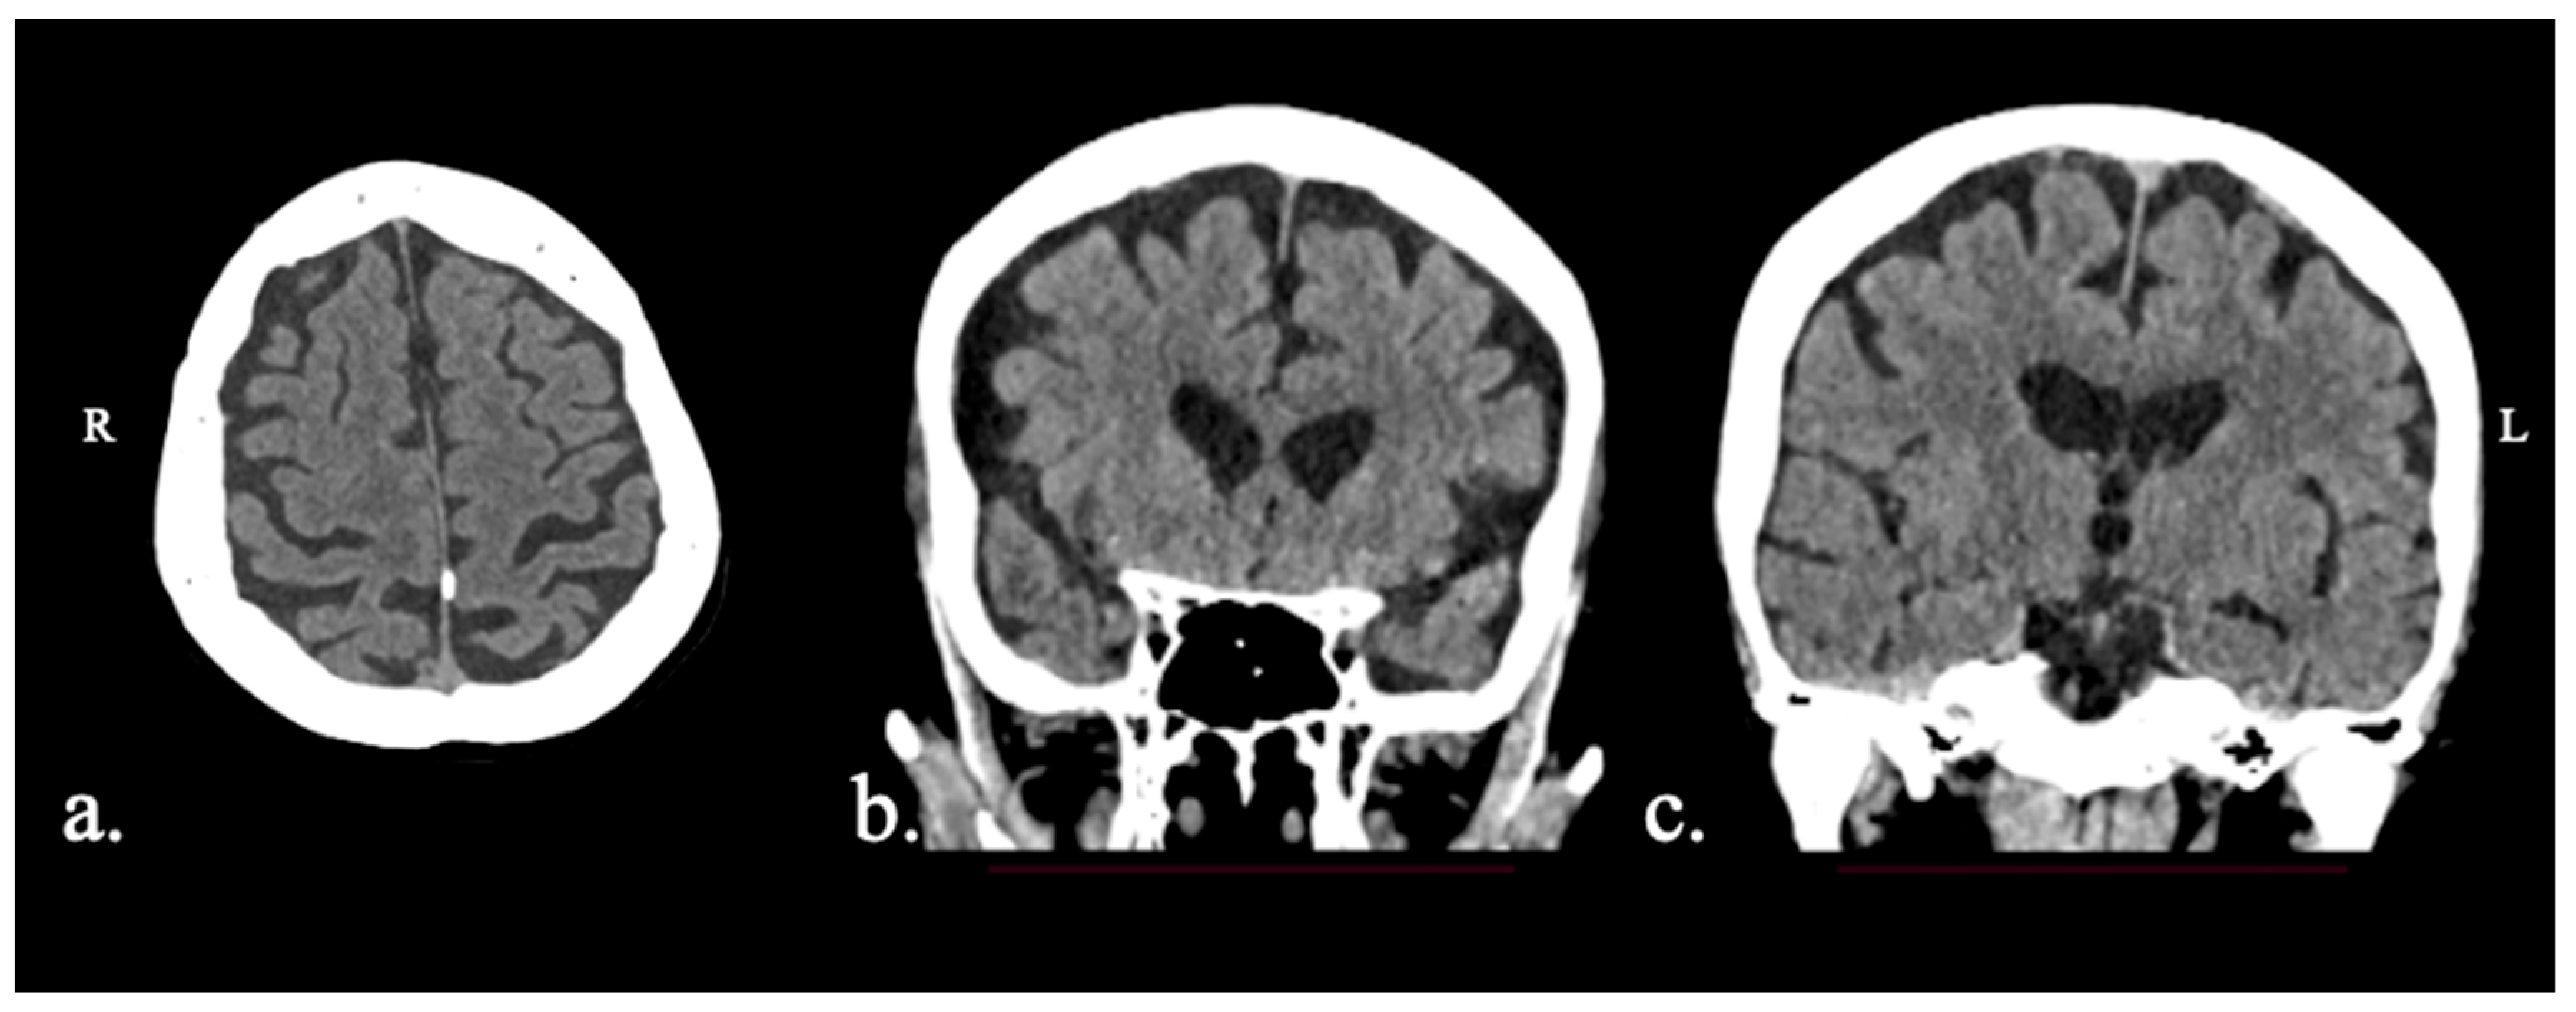

2.1.1. Patient FAY

2.1.2. Patient XTY

2.1.3. Patient ADY

2.1.4. Patient IZS